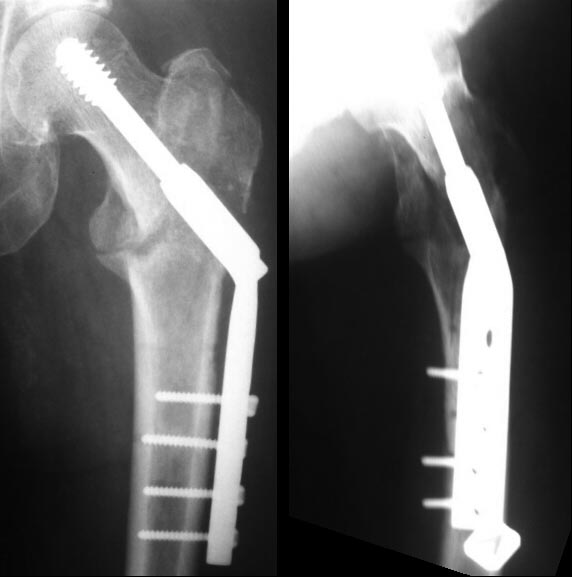

Здравствуйте, уважаемые коллеги.Поделитесь пожалуйста мнением о возможной дальнейшей тактике лечения при данном осложнении. У нас в клинике, в мае 2015 года была прооперирована пациентка 50 лет, страдающая сахарным диабетом, по поводу закрытого чрезвертельного перелома левого бедра со смещением отломков. Был выполнен остеосинтез левого бедра пластиной DHS. Через 3 недели после выписки, в проекции дистального конца пластины сформировались 2 свища с серозно-гнойным отделяемым. Через 1,5 месяца после операции пациентка была госпитализирована в наше отделение. При поступлении у пациентки отмечался умеренный отек мягких тканей в области левого бедра, два свищевых хода с серозно-гнойным отделяемым. Гиперемии в области п\о рубца не было. В отделение была проведена антибактериальная терапия соответственно результатам посева. На фоне лечения свищи закрылись, пациентка не лихорадит. Была выписана из стационара. Что делать дальше?Оставить так и ждать сращения, которое в условиях инфекции и нестабильной фиксации может и не наступить.Или же необходимо оперативное лечение, какая тактика?К сожалению не могу предоставить фистулограммы, но на них контраст распространяется вдоль пластины и заполняет дефект в области большого вертела.Заранее спасибо!

Вертельные переломы хорошо срастаются, но допущенная небольшая флекcия изменила вектор динамического винта и сыграла против скольжения. С момента фиксации прошло достаточное время, и перелом должен срастаться хотя бы частично! Это подтверждается позицией DHS, который, несмотря на сломанные винты, не изменил позицию! Ложный сустав в этой области характерен более драматической картиной, но для уточнения можно сделать КТ!

Полностью согласен с Джолдасом в оценке причины несращения - о неидеальной постановки DHS говорит неплотное прилегание пластины, а значит динамической компрессии не получилось. А вот по дальнейшей тактике, у пациентки с диабетом, я бы убрал конструкцию сразу и бусы.

В нашем примере удаление пластины было произведено из-за поздней инфекции на фоне сросшегося перелома. На месте винта в шейке образовался огромный костный дефект и для профилактики стрессового перелома установили “колбаску” из остатка цемента с антбиотиком. Следующую операцию закончили замещением костного дефекта пластикой из губчатой аллокости, которая была забита в дефект.

Учитывая, что осложнение случилось в раннем периоде, т.е в фазе сращения, надо постараться довести консолидацию без удаления конструкции. Цемент с антибиотиком и неоднократные (I&D) создадут условия против инфицирования раны, а также условия для сращения!